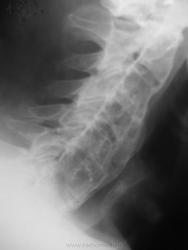

Скованность позвоночника, ограничение подвижности позвоночника. Ваше мнение?

Немного сомневаюсь, но что то крестцово подвздошные сочленеия слабо изменены, справа просматривается даже не в стандартной укладке, да и дугоотростчастый сустав просматривается справа в сегментеL4-5, с чего бы он сохранился при таком распространеиии... Есть над чем подумать. А так, с первого взгяда очень даже похоже.

Классно "похулиганили", теперь то уж точно не поверю, что Бехтерева...это опять Форестье...

По поводу шейного отдела - не уверен, что там полость, структуризация и псевдополостность, очевидно, обьясняются длительностью процесса и слоями окостенения, вроде луковичных.

Написано было "пространство", а пространство, не есть синоним "полости".

Виноват..."полость" додумал уже сам...конечно логичнее - "пространство"....